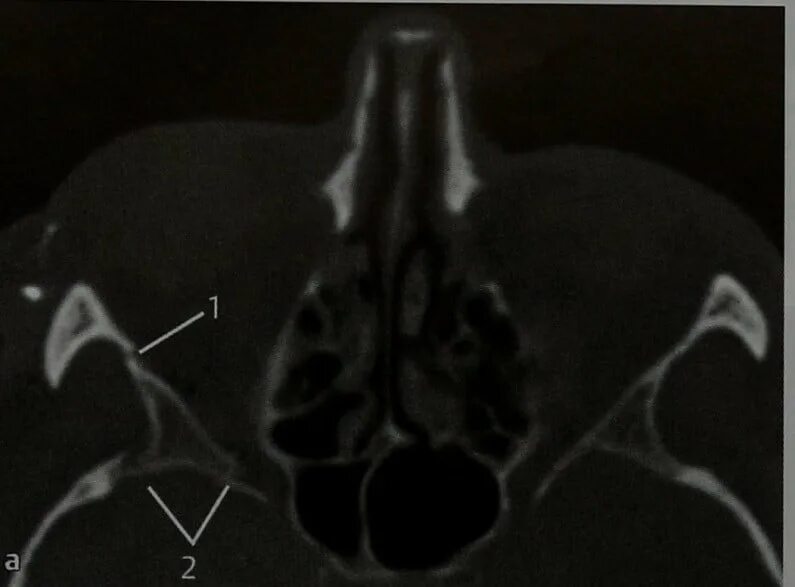

Перелом мрт или кт